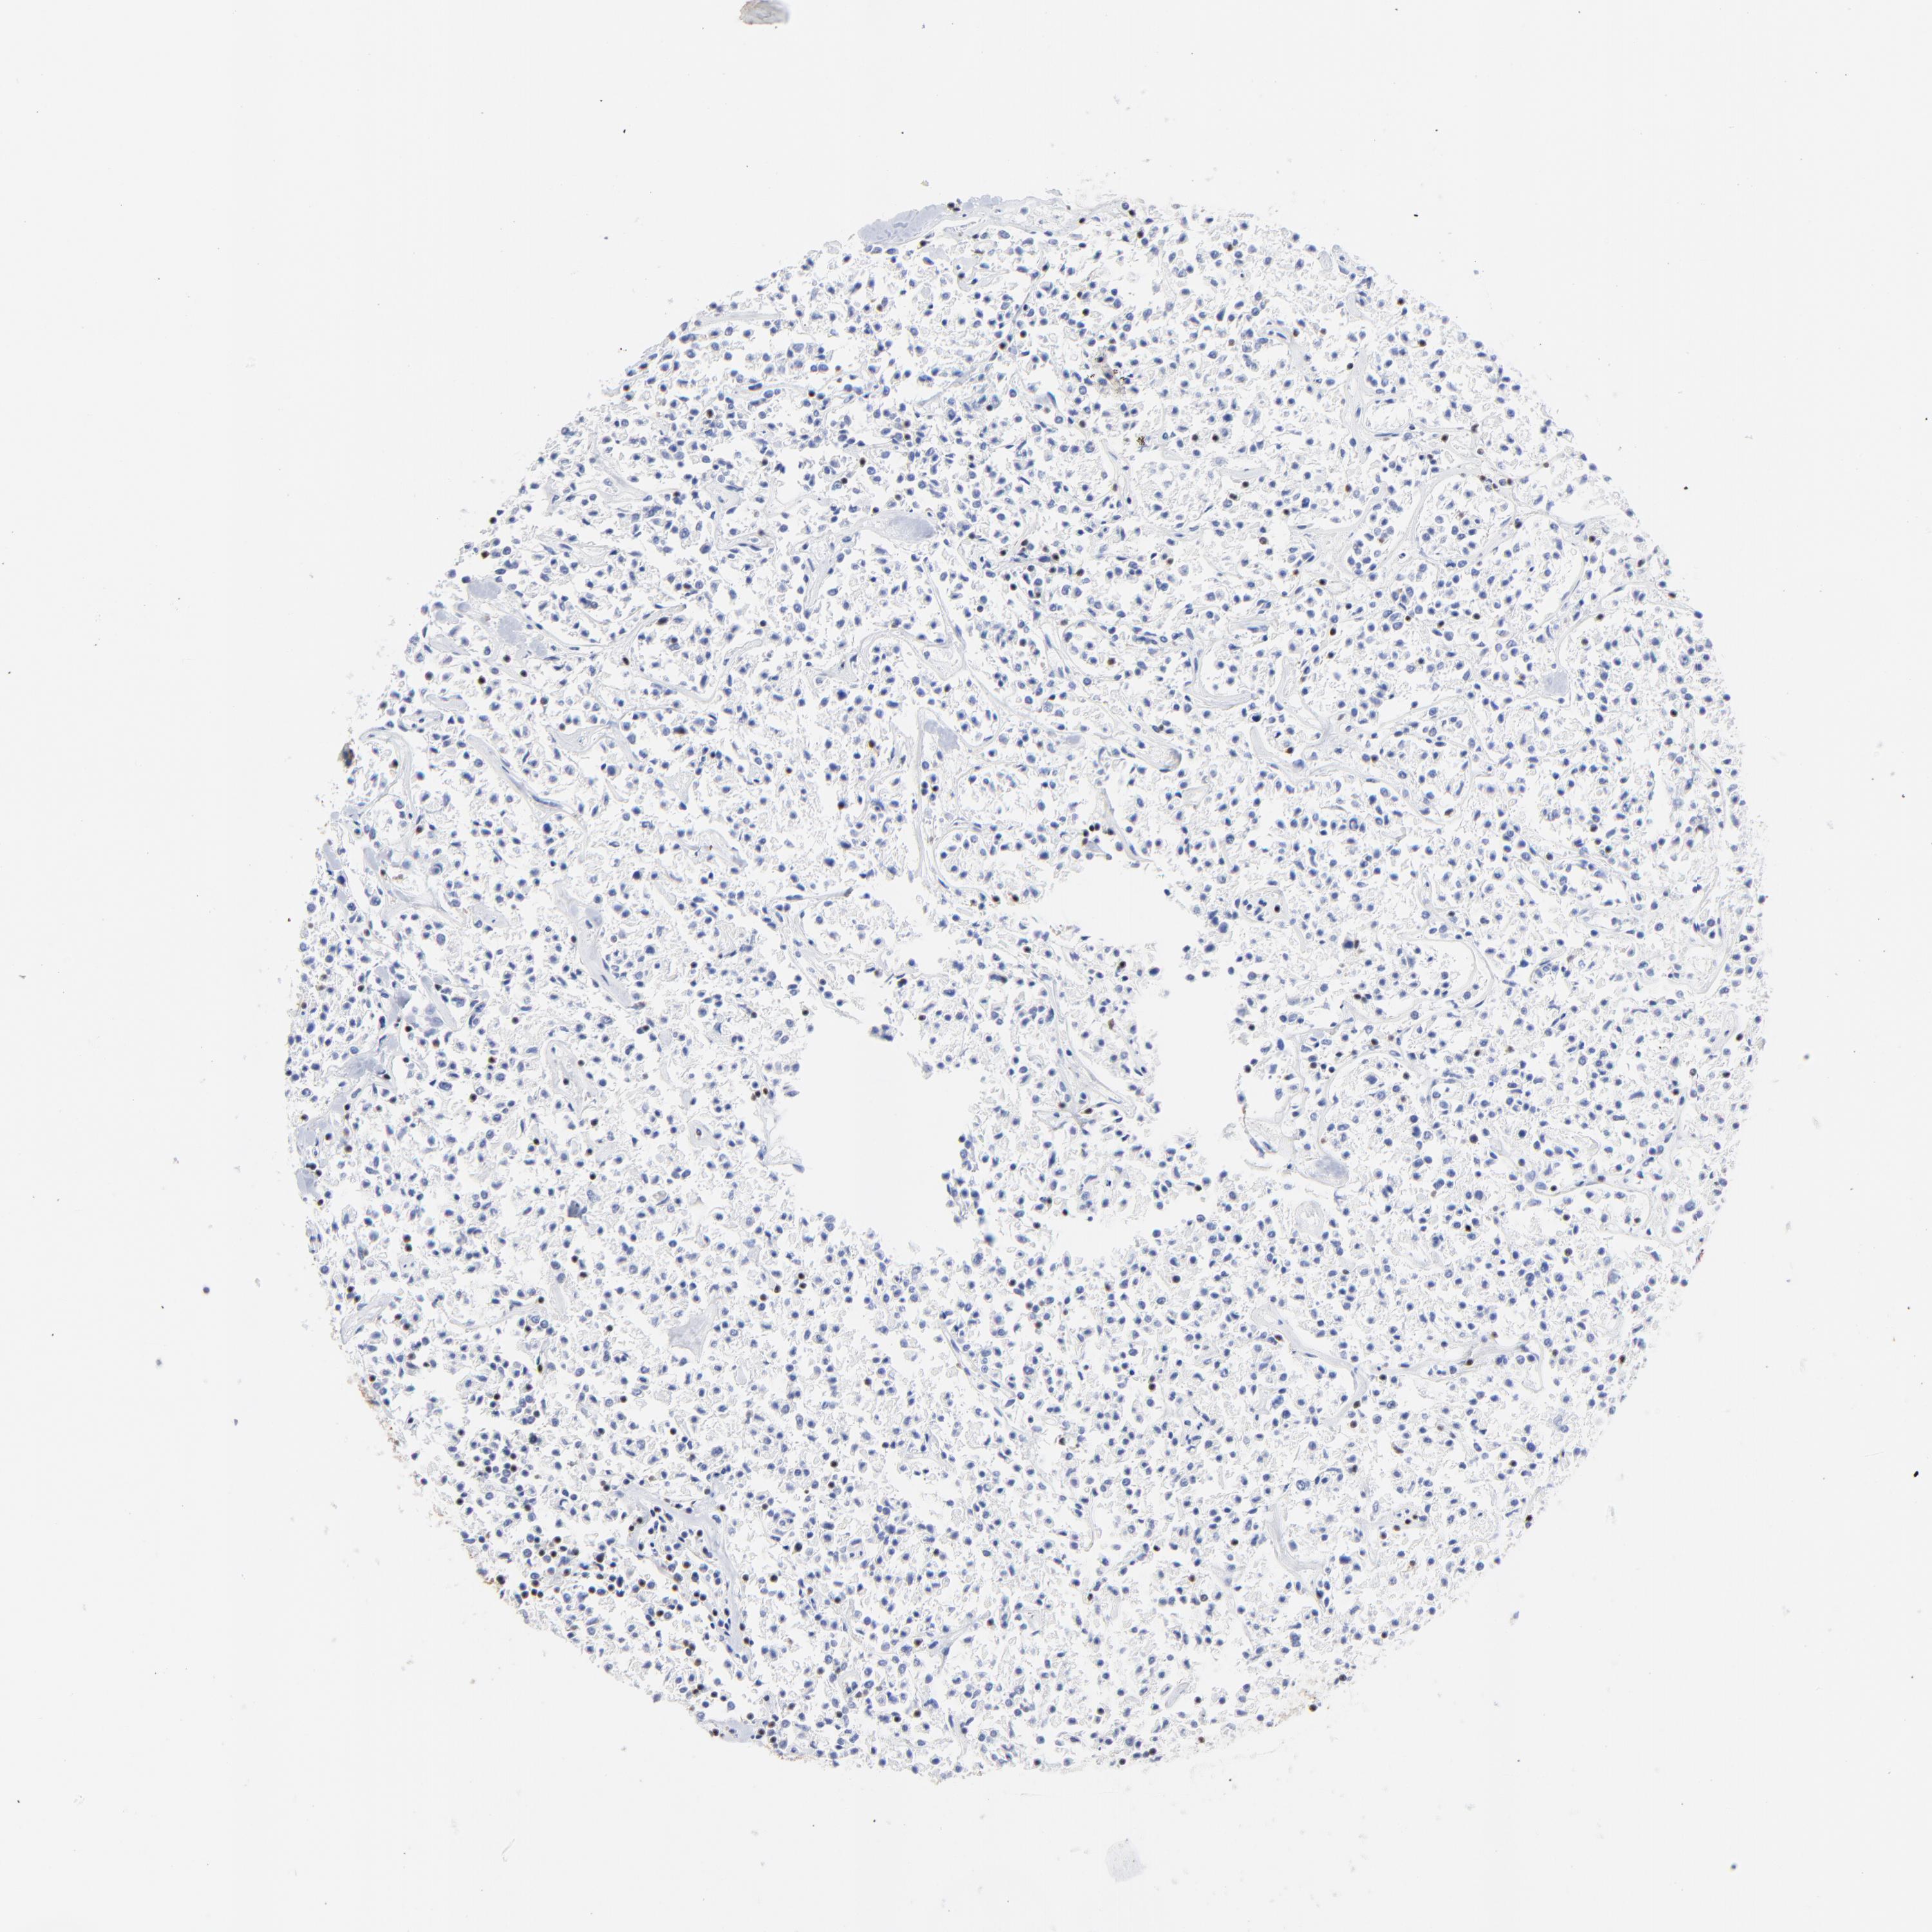

CANCER LYMPHOMA Show tissue menu

LYMPHOMA - Protein expressioni

A mouse-over function shows sample information and annotation data. Click on an image to view it in a full screen mode. Samples can be filtered based on level of antibody staining by selecting one or several of the following categories: high, medium, low and not detected. The assay and annotation is described here.

Antibody stainingi

Antibody staining in the annotated cell types in the current human tissue is reported as not detected, low, medium, or high, based on conventional immunohistochemistry profiling in selected tissues. This score is based on the combination of the staining intensity and fraction of stained cells.

Each image is clickable and will lead to virtual microscopy that enables deeper exploration of all samples and also displays staining intensity scores, fraction scores and subcellular localization as well as patient and tissue information for each sample.

Antibody HPA003134

Malignant lymphoma, non-Hodgkin's type, High grade

Hodgkin's disease, NOS

Malignant lymphoma, non-Hodgkin's type, Low grade